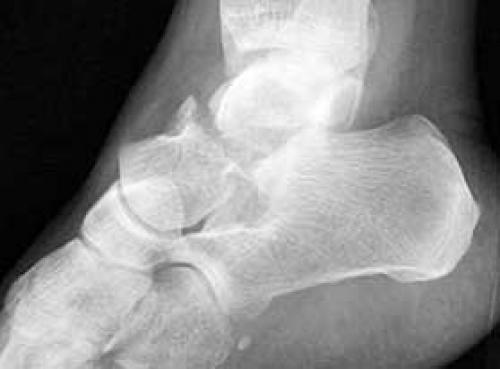

Приходится сталкиваться с переломовывихами: при отламывании одной или обеих щиколоток ноги, они теряют способность фиксировать блок, таранная кость вывихивается и смещается, усложняя лечение.

Рис3. а. перелом наружной лодыжки, разрыв синдесмоза и делтовидной связки, подвывих стопы кнаружи. б. перелом таранной кости.

Подобные травмы опасны нарушением кровоснабжения костной ткани, что становится причиной асептического некроза (таранной кости) и сильно усложняет работу врачей.